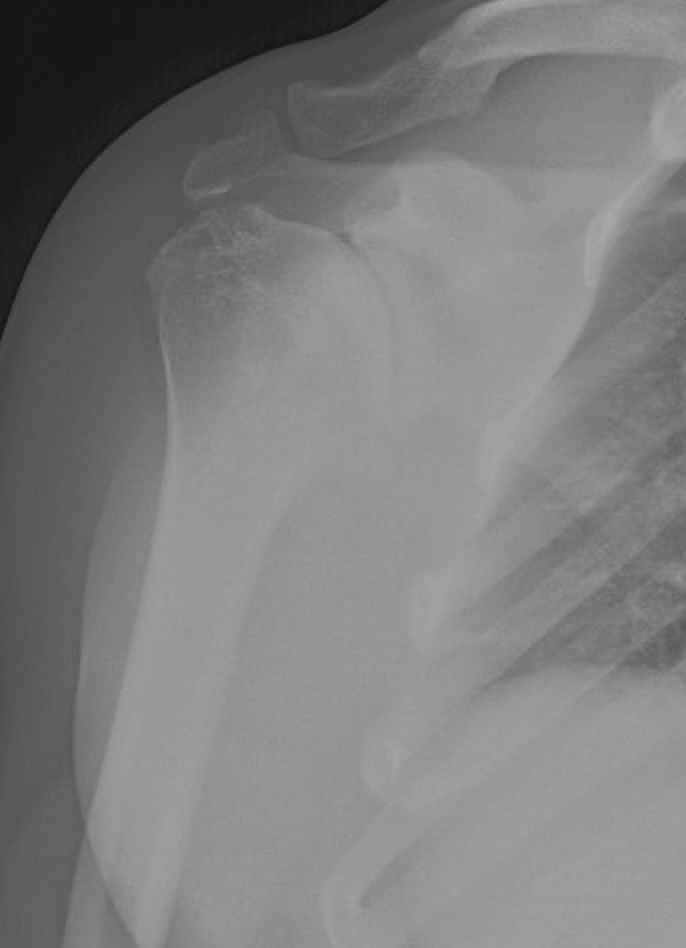

Shoulder Arthritis / Rotator Cuff Tears causes of shoulder pain Weight Training With Shoulder Arthritis If your workout causes pain in the affected joints, you may need to scale back the weights or choose other exercises. Learn the best exercises for shoulders with arthritis, how. exercising can help you relieve arthritis pain. The most beneficial types of exercise for arthritis include: weight training can be helpful, as stronger muscles can take some of. Weight Training With Shoulder Arthritis.